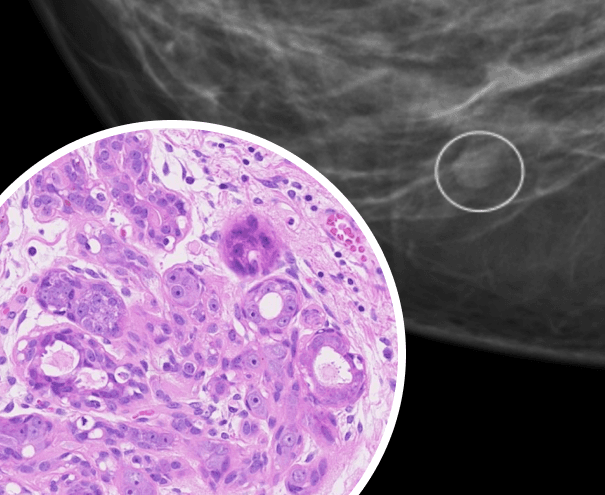

Курс посвящён вопросам классификации и стадирования доброкачественных, прединвазивных и злокачественных опухолей молочной железы в контексте корреляции с лучевыми методами исследования.

На курсе разберёмся в том, как взаимосвязана лучевая и морфологическая картина предопухолевых и опухолевых поражений, а также отработаем теорию на практических примерах.